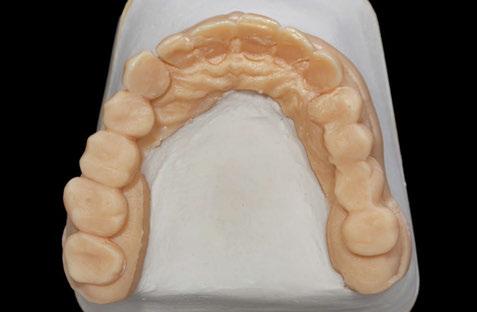

Figuras 11 y 12. Modelos realizados por CAD/CAM con los encerados de los dientes a reponer en los sectores posteriores mandibulares, montados en el articulador para generar una oclusión óptima.

Figuras 13-15. Imágenes del cone-beam de planificación de los cortes mandibulares de los tres implantes de 4,5 mm de longitud. Como podemos observar en los tres casos, la atrofia en altura es muy llamativa, habiéndose necesitado procedimientos regenerativos previos en caso de haber colocado implantes de longitud convencional.